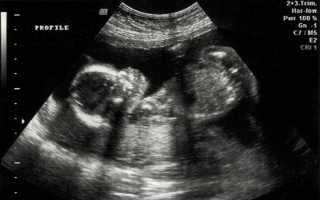

Определение пола ребёнка по УЗИ — важный аспект пренатальной диагностики, интересующий будущих родителей. Ультразвуковое исследование позволяет узнать, кто появится на свет — мальчик или девочка, а также подготовиться к встрече с малышом, выбрав имя и необходимые вещи. В статье рассмотрим, как происходит определение пола на УЗИ, факторы, влияющие на точность результатов, и оптимальные сроки для проведения процедуры.

Чтобы определить, что ваш ребенок – мальчик, врачу необходимо увидеть пенис и мошонку, расположенные между ног малыша. Обычно эти признаки становятся заметными примерно с 20-й недели беременности, хотя у некоторых мальчиков они могут проявиться и раньше.

Важно не спутать пуповину с пенисом, однако современные ультразвуковые технологии позволяют врачу легко различать эти два элемента. Если ультразвуковое оборудование оснащено цветовым допплером, это значительно упрощает задачу, так как цветовой допплер отображает кровоток и помогает четко отличить пуповину от пениса.

Врачи отмечают, что определение пола ребенка с помощью УЗИ является распространенной практикой, но требует внимательности. Современные ультразвуковые технологии позволяют с высокой точностью выявлять пол плода, начиная с 12-14 недель беременности. Тем не менее, специалисты подчеркивают, что точность результатов может зависеть от опыта врача, качества используемого оборудования и положения плода во время обследования.

Определение пола ребёнка по УЗИ является одной из наиболее обсуждаемых тем в акушерстве. Эксперты отмечают, что точность определения пола на ранних сроках беременности может варьироваться. Наиболее достоверные результаты, как правило, получают на сроке 18-20 недель, когда половые органы становятся более различимыми. Однако даже в этот период возможны ошибки, связанные с положением плода и качеством оборудования. Специалисты подчеркивают, что важно помнить о том, что УЗИ — это не 100% гарантия, и в некоторых случаях могут возникать неожиданные результаты при рождении. Кроме того, эксперты призывают родителей не зацикливаться на поле ребёнка, а сосредоточиться на его здоровье и благополучии.